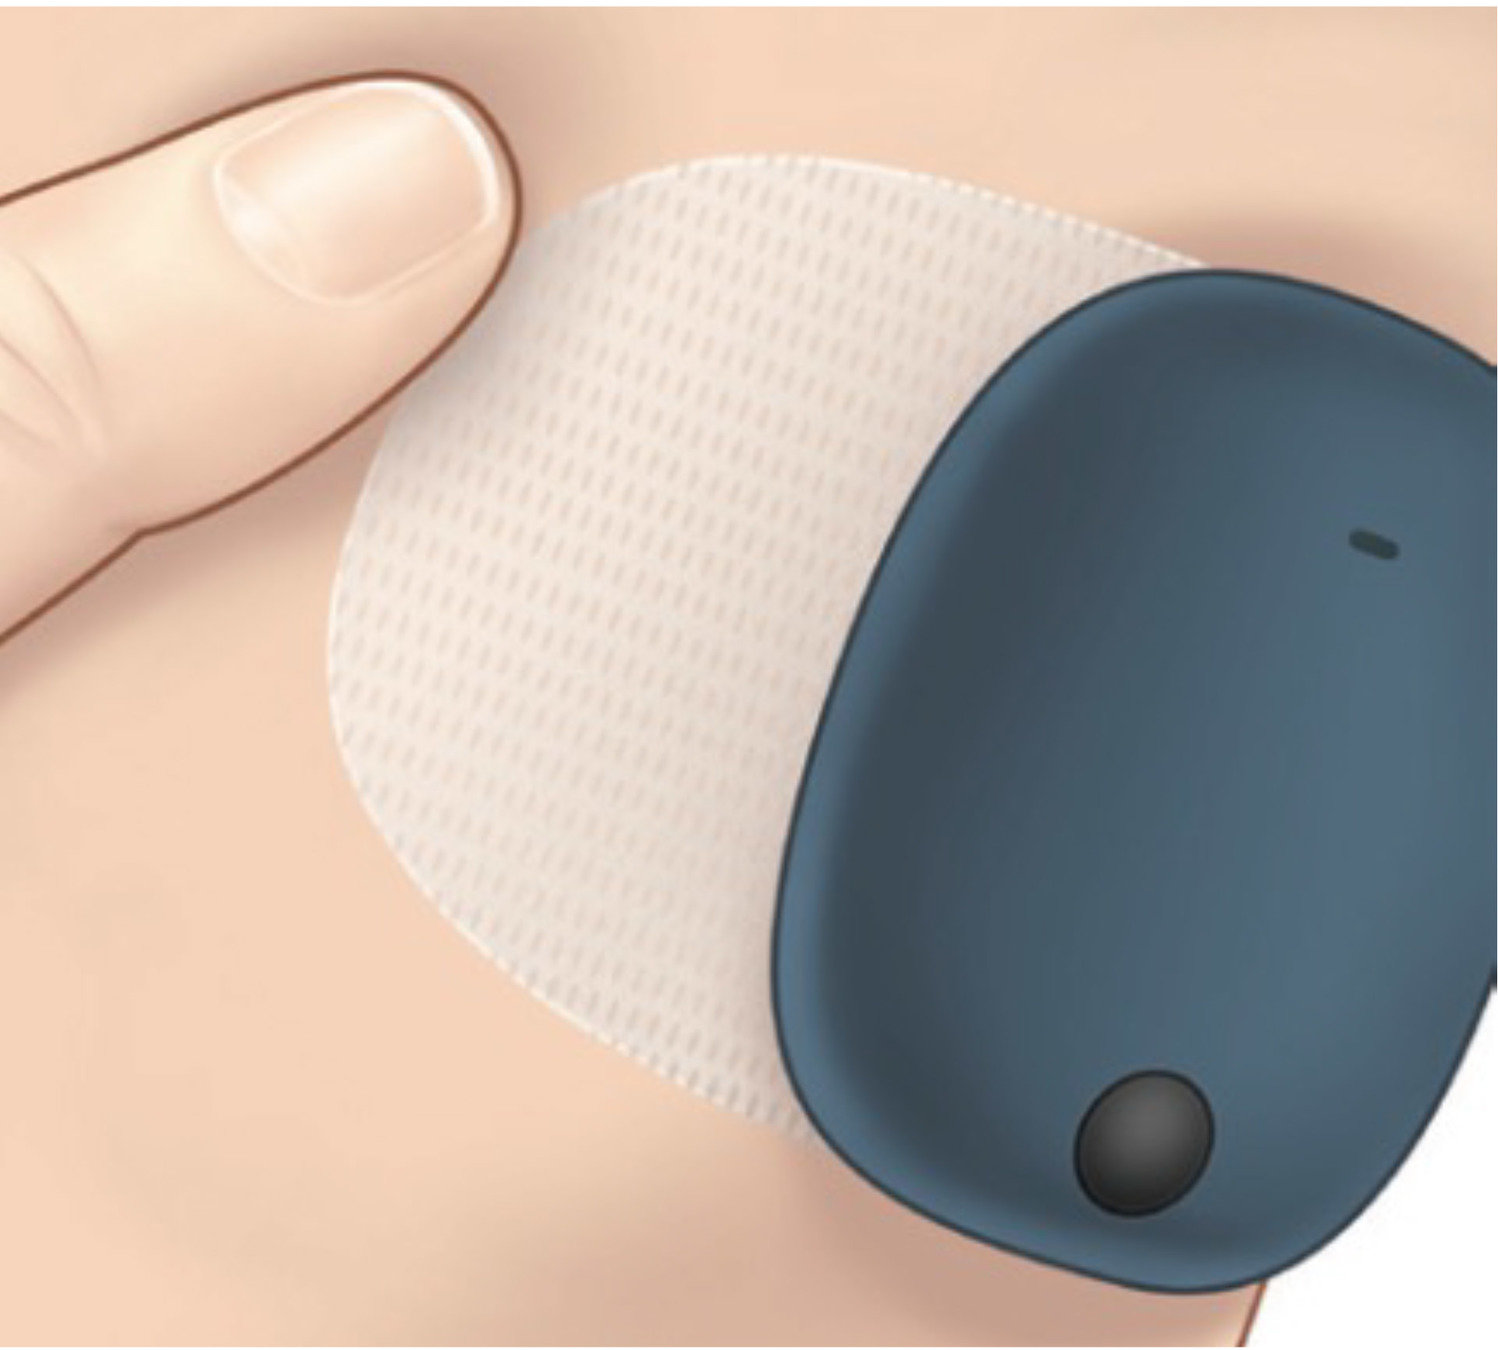

El paso 2 es colocar el transmisor inteligente sobre el parche adhesivo.

Coja un parche adhesivo y retire el papel protector con el logotipo de Eversense®.

El centro del parche es adhesivo

y es donde deberá colocar

el transmisor inteligente, tal

como se indica en la foto.

Presione el transmisor inteligente con firmeza para pegarlo al adhesivo.

A continuación, retire el trozo más grande del protector trasero transparente que queda en

el parche adhesivo.

Ahora estará listo para el paso 3:

colocar el transmisor inteligente Eversense® E3 sobre el sensor Eversense® E3.

Si tiene una cinta de vendaje en el brazo, tendrá que quitársela para poder ver el apósito Tegaderm.

Sostenga el transmisor inteligente con el adhesivo como se muestra, con los lados del parche adhesivo hacia atrás. Si se pueden ver, utilice las marcas de las esquinas del transmisor inteligente que tiene en la piel para colocar el transmisor inteligente hacia la mitad superior del apósito Tegaderm.

Tenga en cuenta que el transmisor inteligente debe tocar el brazo.